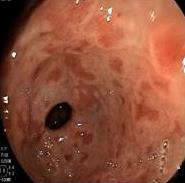

• 色素内镜和窄带成像技术联合放大内镜对早期结直肠癌及癌前病变的诊断价值研究

摘要:目的 探究色素内镜(CE)和窄带成像技术(NBI)联合放大内镜(ME)对早期结直肠癌及癌前病变的诊断价值研究。方法 选取2023年8月-2024年7月于该院接受检查的疑似早期结直肠癌及癌前病变的患者160例。采用四格表法,分析NBI-ME和CE-ME检测早期结直肠癌及癌前病变的敏感度、特异度和准确度;采用Kappa一致性检验,分析CE-ME和NBI-ME诊断早期结直肠癌及癌前病变与病理检查的一致性。结果 病理结果显示,良性病变52例,癌前病变90例,结直肠癌18例。CE-ME检测结果显示,良性病变43例,癌前病变101例,结直肠癌16例,漏诊率为33.33%;CE-ME诊断早期结直肠癌及癌前病变与病理检查的一致性中度(Kappa = 0.605,P < 0.01),敏感度为66.67%,特异度为97.18%,准确度为93.75%。NBI-ME检查结果显示,良性病变43例,癌前病变100例,结直肠癌17例,漏诊率为16.67%,NBI-ME诊断早期结直肠癌及癌前病变与病理检查的一致性较高(Kappa = 0.714,P < 0.01),敏感度为88.33%,特异度为98.59%,准确度为96.88%。CE-ME与NBI-ME两者联合检查结果显示,良性病变56例,癌前病变86例,结直肠癌18例,漏诊率为5.56%,两者联合诊断早期结直肠癌及癌前病变与病理检查的一致性极高(Kappa = 0.857,P < 0.01),敏感度为94.44%,特异度为99.30%,准确度为98.75%,高于CE-ME和NBI-ME单独检查。结论 CE和NBI联合ME对早期结直肠癌及癌前病变具有较高的诊断价值。值得应用于临床。